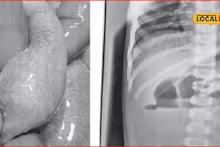

डॉ. तोतला यांनी त्वरित प्राथमिक चाचण्या करून तातडीने शस्त्रक्रिया करण्याचा निर्णय घेतला. डिहायड्रेशन कमी करण्यासाठी सलाईन व औषधे देऊन बाळाला स्थिर करण्यात आले. दुसऱ्या दिवशी पोट उघडल्यावर त्यांना लहान आतड्यांमध्ये सूज आणि अडथळा दिसला. संपूर्ण 24 फुटांची आतडी तपासल्यावर एका विशिष्ट ठिकाणी काहीतरी अडकल्याचे लक्षात आले.

अडीच तासांच्या अथक शस्त्रक्रियेनंतर, अडकलेल्या जागेवर चिरा मारून 3 सेंटीमीटरचा फुगलेला जेली बॉल यशस्वीपणे बाहेर काढण्यात आला. बॉल बाहेर पडताच साचलेले मलही बाहेर पडले. शस्त्रक्रियेनंतर बाळाला नऊ टाके घालण्यात आले आणि तीन दिवस अतिदक्षता विभागात (ICU) ठेवण्यात आले. डॉ. तोतला यांना सहयोगी शल्यचिकित्सक डॉ. अर्जुन पवार आणि भूलतज्ज्ञ डॉ. श्रीगोपाल भट्टड यांचे मोलाचे सहकार्य लाभले.

"ज्येष्ठ बालशल्यचिकित्सक डॉ. तोतला यांनी सांगितले की, "बाळाने गिळलेल्या जेली बॉलला आतड्यांमध्ये पाण्याचा संपर्क मिळताच तो फुगला आणि अडथळा निर्माण झाला. त्यामुळे अन्नपचन थांबून उलट्यांतून अन्न बाहेर पडत होते. बाळाची स्थिती पाहून शस्त्रक्रिया करणे अत्यंत गरजेचे होते आणि ही मोठी 'रिस्क' होती, पण यशस्वी झाली."